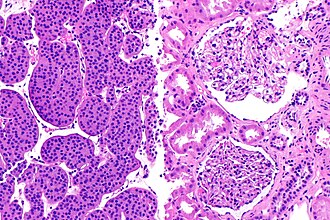

Renal oncocytoma (left of image) and normal kidney (right of image). Kidney biopsy. H&E stain. | |

Renal oncocytoma is a benign kidney tumour that is removed to exclude malignancy.

- Eosinophilic cytoplasm - slightly granular key feature.

- Cells arranged in nests.

- Nuclei uniform and round.[2]

- Slightly enlarged nuclei, but no significant pleomorphism (size variation) - important.‡

- May look like eosinophilic variant of chromophobe RCC -- this is the main DDx.

- Oncocytoma typically has: no perinuclear clearing, no raisinoid nuclei, rare or no binucleation.